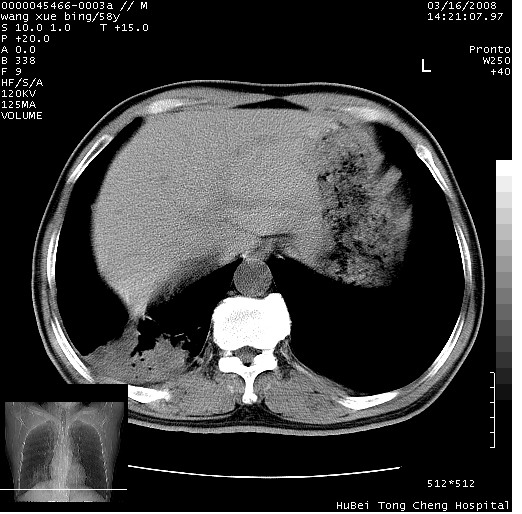

胸部ct轴位平扫(层厚10mm,螺距1.5,重建间隔10mm),图像如下:

考虑右下肺周围型肺癌并远端阻塞性炎症及胸膜转移

考虑右下肺中心型肺癌并远端阻塞性炎症及胸膜及纵隔淋巴转移

支持癌性空洞并远端阻塞性炎症